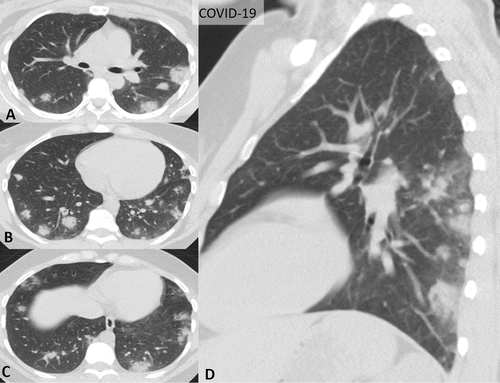

Bien que la tomodensitométrie de dépistage de routine pour l'identification de la pneumonie au COVID-19 ne soit actuellement pas recommandée par la plupart des sociétés de radiologie, le nombre de scanners pratiqués chez les patients suspectés de COVID-19 a augmenté. Certains patients attribuent leur âthologie à la pneumonie au COVID-19, obligeant les radiologistes à mentionner spécifiquement le COVID-19 comme possibilité de diagnostic différentiel.

La pneumonie au COVID-19, qui a un taux de mortalité élevé chez les personnes âgées et celles atteintes de diabète, d'hypertension et d'autres comorbidités, se propage rapidement dans les communautés. Par conséquent, l'inclusion fréquente du « COVID-19 » dans le compte rendu de radiologie pourrait déclencher une cascade d'événements incluant des mesures de contrôle des infections et de l'anxiété pour le clinicien et le patient. De plus, les caractéristiques au scanner du COVID-19 peuvent s’agréger de manière significative à d'autres causes de lésions pulmonaires aiguës et de pneumonie, ce qui complique les interprétations.

La déclaration de consensus, élaborée par des experts de neuf centres médicaux universitaires des États-Unis, vise à aider les radiologues à reconnaître les résultats de la pneumonie au COVID-19 et à fournir des conseils sur l’annonce des résultats du scanner potentiellement associés au COVID-19, à travers notamment un langage normalisé pour réduire la variabilité des comptes rendus. Un langage d’annonce normalisé améliorera certainement la communication avec les prestataires référents et réduire l'anxiété dans la prise en charge des patients pendant la pandémie.